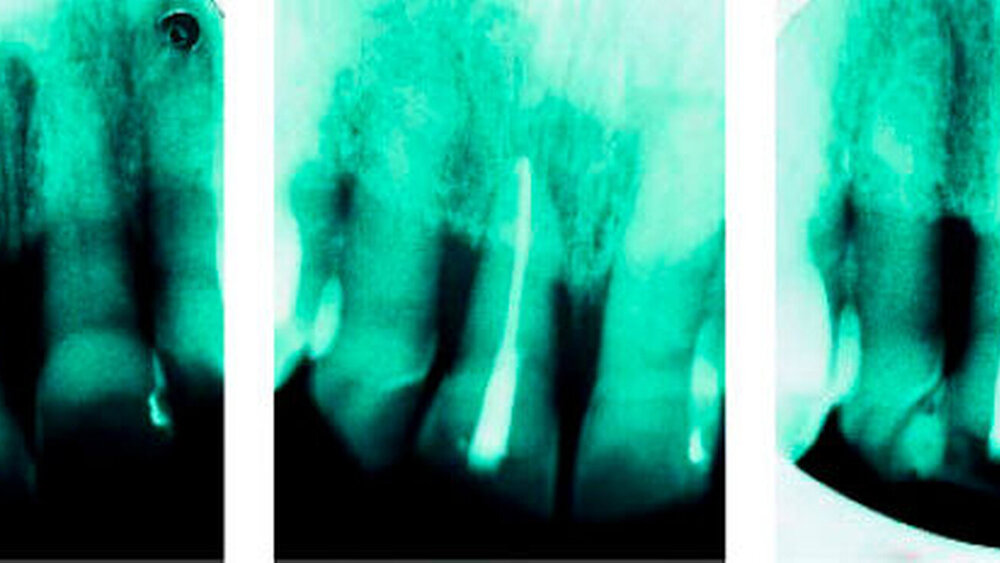

Im folgenden Fall kam Patient A Jahrgang 1924 nach Jahren der Einschleifmaßnahmen und wiederholter Kürzungen der Schneidekante des elongierten Zahnes 11 am 18. Dezember 1997 mit einem Taschenabszess in die Praxis. Zahn 11 wies Lockerungsgrad III auf, mit elf Millimetern Taschentiefe labial und zehn Millimetern mesial und distal. Der horizontale und vertikale Knochenverlust ist auf Aufnahme 1 zu erkennen. Da die Nachbarzähne klinisch nur Lockerungsgrad I aufwiesen und karies- und füllungsfrei waren, sollte ein Totalverlust des Zahnes auch wegen oben angesprochener Folgeproblematik vermieden werden. Bei der folgenden Vitalexstirpation und Kanalaufbereitung kam es zu einem Spontanausfall des Zahnes, so dass die weitere Wurzelkanalbehandlung und -füllung extraoral erfolgen mussten.

Eine abschließende Schienung in Kombination mit einem Schneidekantenaufbau mittels Composite-Kunststoff (Kerr Herculite) sorgte für einen stabilen Verbund. Die Abbildungen auf Seite 48 zeigen den Zustand nach vier Jahren (10. Juli 2001). Deutlich erkennbar ist der nun ausreichende Halt im Alveolarkamm. Anzeichen von Resorptionen sind nicht erkennbar. Klinisch ist der Zahn ohne Lockerungsgrad. Der Klopfschall lässt eine Ankylosierung des Zahnes vermuten.